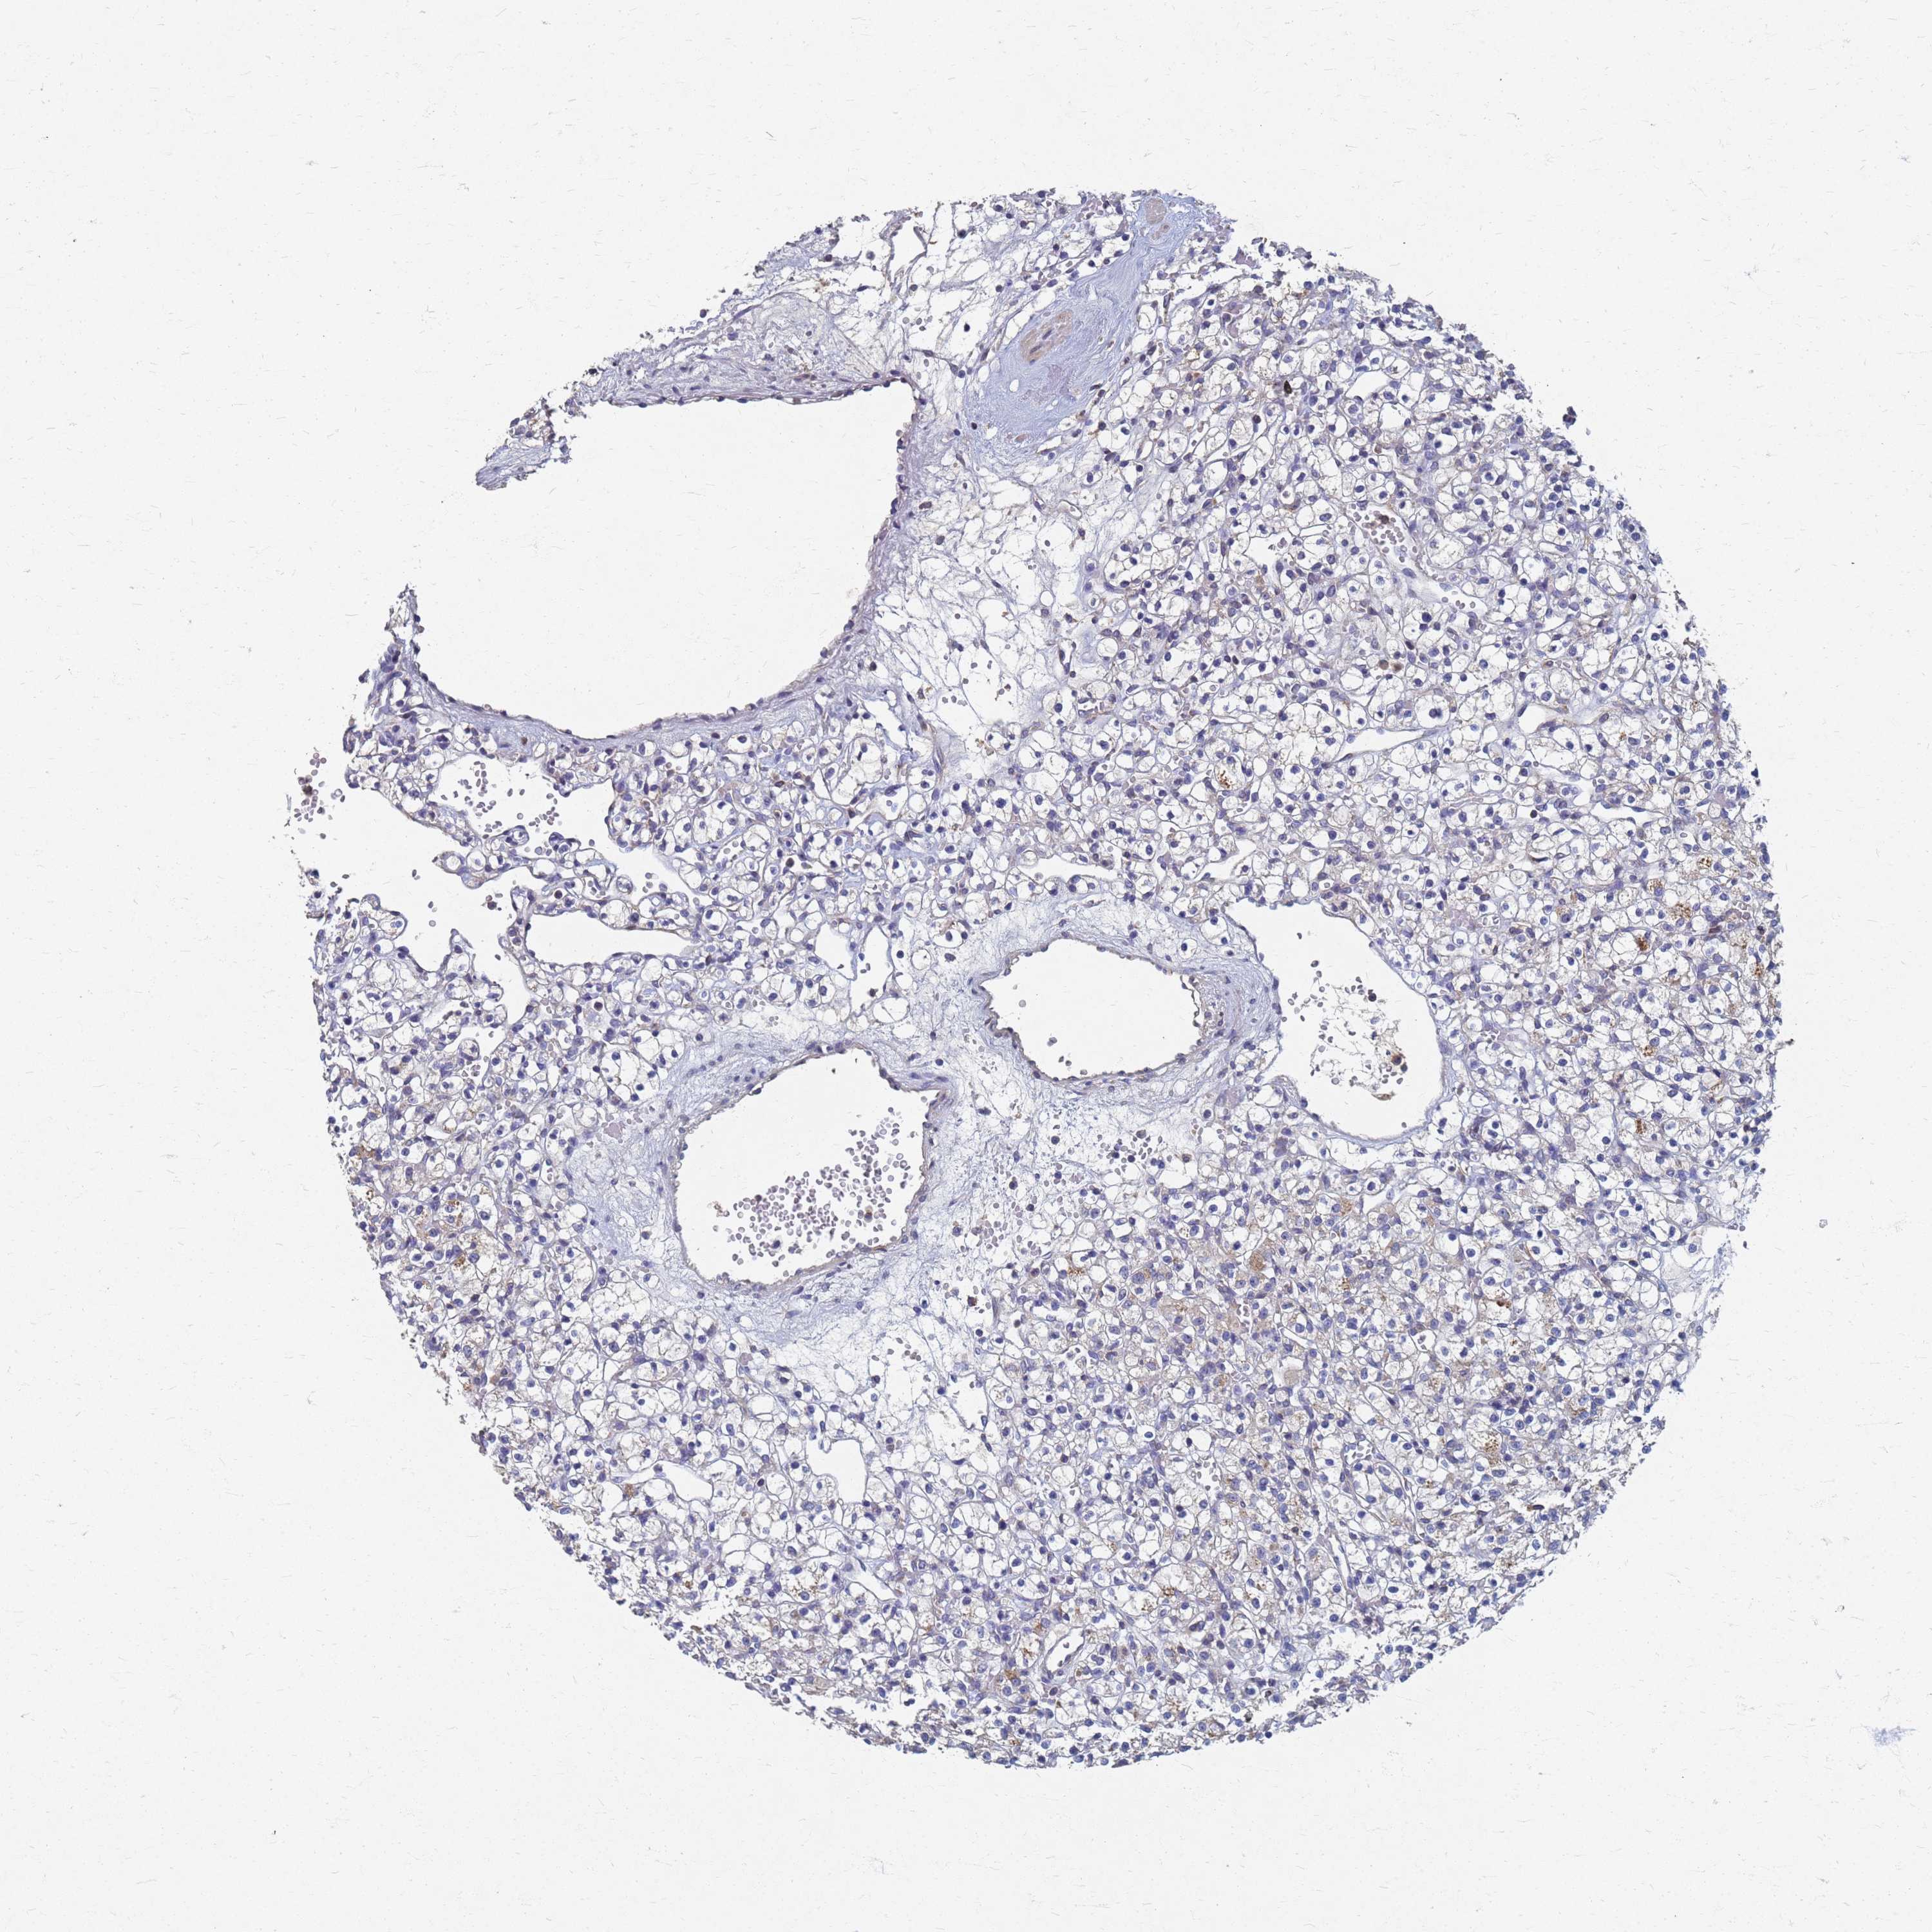

KIDNEY RENAL CLEAR CELL CARCINOMA (TCGA) - Interactive survival scatter ploti

The Survival Scatter plot shows the clinical status (i.e. dead or alive) for all individuals in the patient cohort, based on the same data that underlies the corresponding Kaplan-Meier plots. Patients that are alive at last time for follow-up are shown in blue and patients who have died during the study are shown in red.

The x-axis shows the expression levels (FPKM) of the investigated gene in the tumor tissue at the time of diagnosis. The y-axis shows the follow-up time after diagnosis (years). Both axes are complimented with kernel density curves demonstrating the data density over the axes. The top density plot shows the expression levels (FPKM) distribution among dead (red) and alive patients (blue). The right density plot shows the data density of the survived years of dead patients with high and low expression levels respectively, stratified using the cutoff indicated by the vertical dashed line through the Survival Scatter plot. This cutoff is automatically defined based on the FPKM cutoff that minimizes the p-score. The cutoff can be changed by dragging the vertical line or by entering a cutoff value in the square labeled "Current cut-off".

Under the Survival Scatter plot the p-score landscape (black curve; left axis) is shown together with dead median separation (red curve; right axis). Dead median separation is the difference in median mRNA expression between patients who have died with high and low expression, respectively. It is calculated as follows: median FPKM expression of dead patients with high expression - median FPKM expression of dead patients with low expression. This is intended to aid the user in visually exploring custom cutoffs and the associated p-scores and dead median separation.

Individual patient data is displayed and can be filtered by clicking on one or more of the category buttons on the top of the page. Categories describing expression level and patient information include: high, low, alive, dead, female, male and tumor stages. The scale of the x-axis can be toggled between linear and log-scale by clicking on the "x log" button. Mouse-over function shows TCGA ID, patient information and mRNA expression (FPKM) for each patient.

& Survival analysisi

Kaplan-Meier plots summarize results from analysis of correlation between mRNA expression level and patient survival. Patients were divided based on level of expression into one of the two groups "low" (under cut off) or "high" (over cut off). X-axis shows time for survival (years) and y-axis shows the probability of survival, where 1.0 corresponds to 100 percent.

KRCC1 is potential prognostic, high expression is favorable in Kidney Renal Clear Cell Carcinoma (TCGA)

Best expression cut offi

: 29.61

Median expressioni

: N/A

Median follow up timei

P scorei

N/A

5-year survival highi

For melanoma and glioma, 3-year survival is shown.

5-year survival lowi

TCGA RNA samplesi

RNA-seq data is reported as average FPKM (number Fragments Per Kilobase of exon per Million reads), generated by the The Cancer Genome Atlas (TCGA) .

Normal distribution across the dataset is visualized with box plots, shown as median and 25th and 75th percentiles. Points are displayed as outliers if they are above or below 1.5 times the interquartile range. FPKM values of the individual samples are presented next to the box plot.

Average pTPM 31.4

Number of samples 521